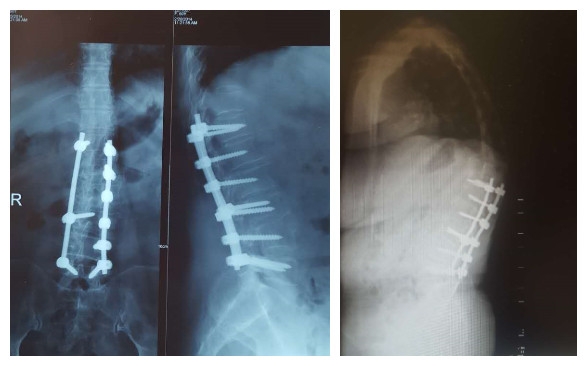

(3)肋骨固定

T10骨盆固定,出现交界性后凸

行翻修手术:T9/10SP截骨,延长到T4固定,预防性双侧肋骨固定(VEPTR)

图32-33 肋骨固定